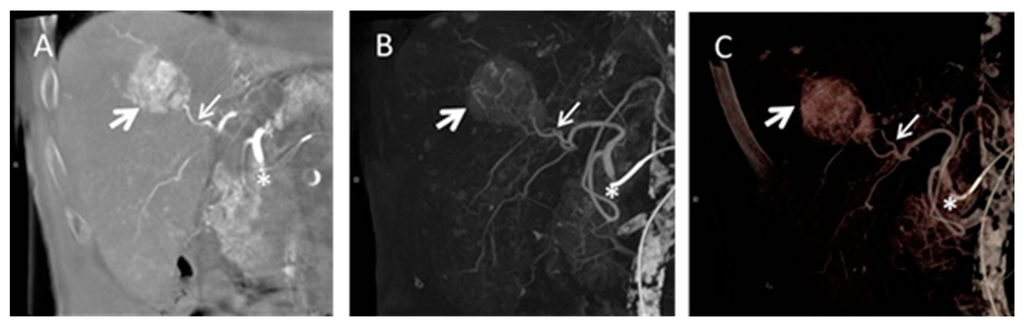

4.4. Cone Beam Computed Tomography in Peri-Procedural Imaging of HCC

- Bapst, B.; Lagadec, M.; Breguet, R.; Vilgrain, V.; Ronot, M. Cone beam computed tomography (CBCT) in the field of interventional oncology of the liver. Cardiovasc. Interv. Radiol. 2015. [Google Scholar] [CrossRef] [PubMed]

- Huppert, P.E.; Firlbeck, G.; Meissner, O.A.; Wietholtz, H. C-arm-CT bei der chemoembolisation von lebertumoren. Radiology 2009, 49, 830–836. [Google Scholar] [CrossRef] [PubMed]

- Lucatelli, P.; Corona, M.; Argirò, R.; Anzidei, M.; Vallati, G.; Fanelli, F.; Bezzi, M.; Catalano, C. Impact of 3D rotational angiography on liver embolization procedures: Review of technique and applications. Cardiovasc. Interv. Radiol. 2015, 38, 523–535. [Google Scholar] [CrossRef] [PubMed]

- Van den Hoven, A.; Prince, J.; de Keizer, B.; Vonken, E.-J.A.; Bruijnen, R.G.; Verkooijen, H.; Lam, M.E.H.; van den Bosch, M.A.J. Use of C-arm cone beam CT during hepatic radioembolization: Protocol optimization for extrahepatic shunting and parenchymal enhancement. Cardiovasc. Interv. Radiol. 2015. [Google Scholar] [CrossRef] [PubMed]

- Kakeda, S.; Korogi, Y.; Ohnari, N.; Moriya, J.; Oda, N.; Nishino, K.; Miyamoto, W. Usefulness of cone-beam volume CT with flat panel detectors in conjunction with catheter angiography for transcatheter arterial embolization. J. Vasc. Interv. Radiol. 2007, 18, 1508–1516. [Google Scholar] [CrossRef] [PubMed]

- Tognolini, A.; Louie, J.D.; Hwang, G.L.; Hofmann, L.V.; Sze, D.Y.; Kothary, N. Utility of C-arm CT in patients with hepatocellular carcinoma undergoing transhepatic arterial chemoembolization. J. Vasc. Interv. Radiol. 2010, 21, 339–347. [Google Scholar] [CrossRef] [PubMed]

- Loffroy, R.; Lin, M.; Rao, P.; Bhagat, N.; Noordhoek, N.; Radaelli, A.; Blijd, J.; Geschwind, J.-F. Comparing the detectability of hepatocellular carcinoma by C-arm dual-phase cone-beam computed tomography during hepatic arteriography with conventional contrast-enhanced magnetic resonance imaging. Cardiovasc. Interv. Radiol. 2012, 35, 97–104. [Google Scholar] [CrossRef] [PubMed]